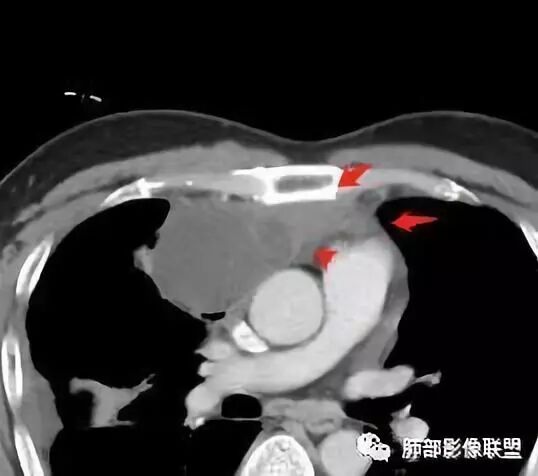

我认为囊张力高,积液中的气体均在周围,外侧、下方,囊内有间隔:各腔密度不一致;提示:囊腔属于前纵隔,不是包裹性积液;现在的问题:囊腔与内侧的病灶是否是一体的

南边:我总觉得这个纵隔内不像是一个肿块的改变,扁平,周围蔓延:有符合炎性的的特点,或者肿瘤的侵犯;但是肿瘤的侵犯,不大符合,实性部位的边缘过于柔和,没有毛糙的侵犯边缘。

2、前纵隔内病灶囊实性混杂密度病灶,囊性病灶主要位于右侧,张力较高,有分隔影,囊壁右侧缘光整,病灶左侧实性部分边界不清明显强化,病灶肺瘤交界面大部分边界清楚,部分模糊。

胸腺瘤/胸腺癌:病灶内那么大的囊,常规考虑B型以上胸腺瘤,囊内有分隔影,病灶周围脂肪间隙模糊,常规考虑侵袭性胸腺瘤或胸腺癌,若侵袭性胸腺瘤,常侵犯胸膜、心包,很少累及肺。胸腺癌易侵犯胸膜、肺并纵隔淋巴结及远处转移。但肺内腺癌形态更符合原发灶。胸膜及叶间裂转移则即可来自肺,也可来自胸腺癌。